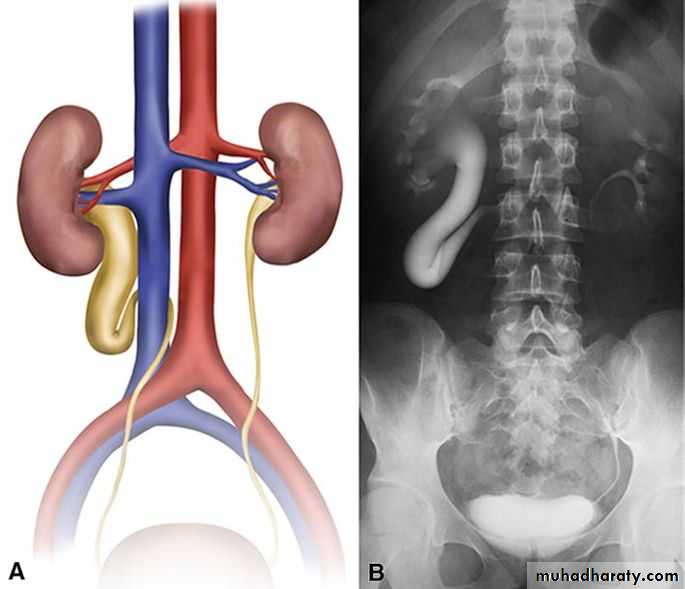

hydronephrosis

Aseptic dilatation of renal pelvis and collecting system

0.6-4.5% antenatal U/S

Several grading system (renal pelvic diameter)

Antenatal U/S

Causes

Transient , physiological , PUJ Ob. , VUR , Megaureter , Ureterocele , PUV